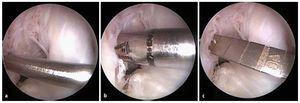

Fig. 12 La guía (a) se introduce en toda su longitud perforando con la broca más delgada (diámetro 4,5 mm) (b). A continuación se mide la longitud del túnel con un medidor de profundidad especial (c). La longitud del túnel varía entre 30 y 45 mm.

Fig. 13 Después de determinar la longitud del túnel se vuelve a insertar la guía dentro del túnel y se ensancha paso a paso a lo largo de los 30 mm distales, hasta conseguir el diámetro del injerto (a). A modo alternativo, también se puede dilatar el túnel con dilatadores femorales (b). Durante el proceso de dilatación, el hueso se comprime en la zona de la pared del túnel. Durante la perforación pueden producirse defectos óseos.

Fig. 14 Representación esquemática del túnel femoral. a Longitud de túnel total. b Longitud del orificio ciego. c Medidor de profundidad.